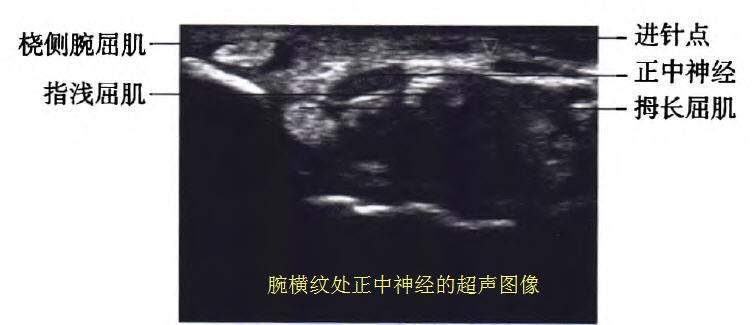

目前腕管综合征治疗方法主要包括佩戴夹板,口服非甾体类药物,神经阻滞治疗,中医疗法以及手术治疗。腕管是由正中神经和九条肌腱组成,包括指浅屈肌、指深屈肌和拇长屈肌,这些肌腱被屈肌支持带包裹,正中神经位于屈肌支持带下方,在桡侧腕屈肌、指浅屈肌、拇长屈肌之间。同时腕管两则伴行着神经和血管。目前神经阻滞正中神经是治疗腕管综合症非常有效的办法之一,超声引导腕管注射在临床医生中逐渐普及。超声引导能够实时、动态显示腕管结构和注射时针的位置。这些优点帮助临床医生在注射过程并避免损伤正中神经、肌腱以及血管,能够选择最佳的路径,及时调整进针路线,最大限度避免对肌腱、神经、血管的损伤,减少盲目穿刺导致的不良反应,同时也提高阻滞的成功率。

超声阻滞方法:所有患者取坐位,肘部以下置于检查床,手背下垫一块折叠的毛巾,采用超声下平面内尺侧入路。采用便携式超声仪高频直线探头,频率6~13 MHz,超声探头常规消毒,患者手腕部皮肤常规消毒后涂无菌耦合剂,探头长轴与手臂垂直,调节超声仪器的增益按钮,选择最清晰的画面,并且从画面中找到类椭圆形状的正中神经。

然后采用平面内技术,在超声的引导下从尺侧人路,针尖从指浅屈肌与指深屈肌之间穿行到达正中神经的神经鞘膜附近。